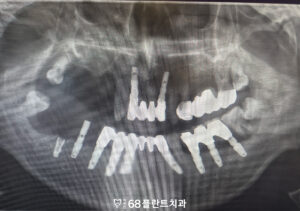

◆ 전 > 후 ◆

치료 마무리 후 사진입니다.

환자분께서는 전체적으로 치아 상태가 좋지 않아

저작에 불편함을 느끼고 계셨으나,

치료 이후 안정적인 기능 회복과 함께

일상적인 식사가 가능해지며

높은 만족도를 보여주셨습니다.